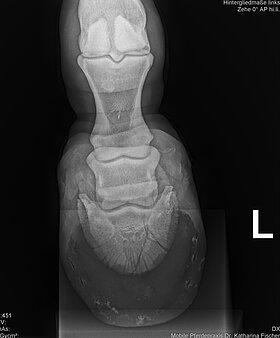

Mit akkubetriebenen Röntgengeräten können wir bei orthopädischen Untersuchungen oder Verletzungen (auch auf der Koppel oder an einem Offenstall) ohne Strom direkt vor Ort röntgen und die Bilder gleich auswerten.